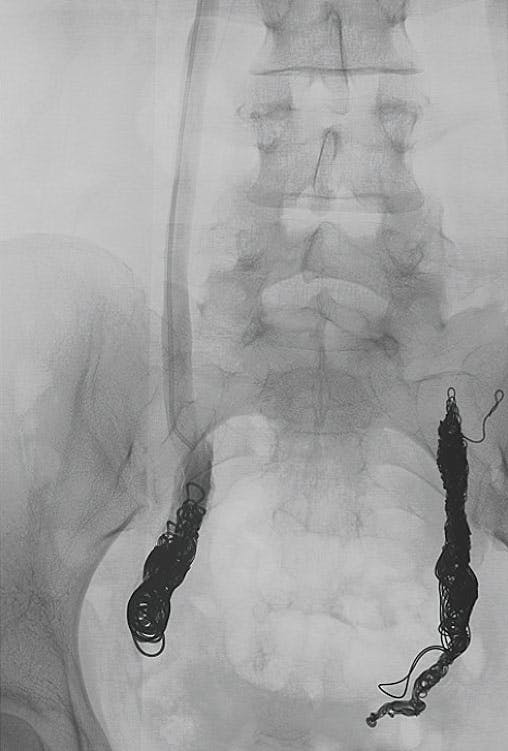

The ovarian vein was cannulated and packed with Ruby Coils (Penumbra, Inc.). We utilized several 14-mm X 60-cm Packing Coils (Penumbra, Inc.) as well as a 12-mm POD® (Penumbra, Inc.) to secure the coils in a cephalad direction. Completion venography showed occlusion of the ovarian vein with excellent packing throughout (Figure 2).

Figure 2. Postembolization venography showing dense packing and complete occlusion of the left ovarian vein using Ruby Coils and a POD.